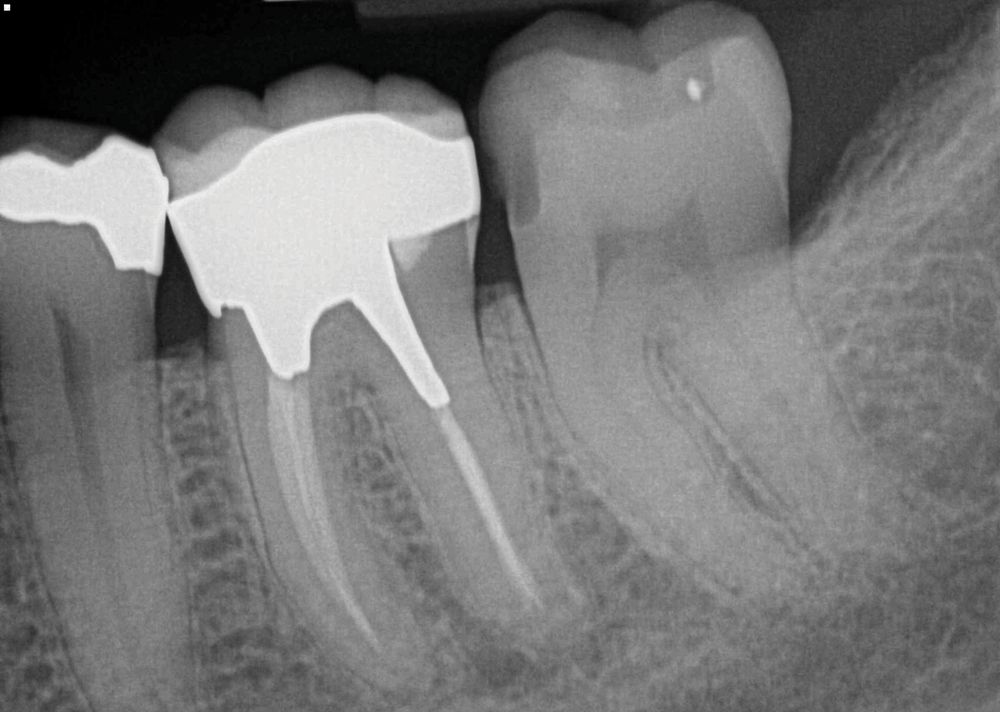

The material used to fabricate a post should be considered as well. Both cast and prefabricated options are available, but there is no consensus regarding the effect of cast versus prefabricated posts on survival rates, and different studies have found opposing results.5,16 The most common materials used in posts are metal and fiber. Both materials have been associated with similar survival rates.17 In teeth with no remaining coronal walls or an absence of ferrule, posts with higher values of elastic modulus, such as fiber posts, have been shown to result in better clinical outcomes when compared with metal posts.18 However, in teeth with at least one remaining coronal wall, restorations with fiber and metal posts demonstrated similar survival rates.18 The choice of which material to use should be based on the specific case and patient factors (Figure 4 and Figure 5).

(4.) Radiographs of teeth treated with prefabricated and custom cast posts, respectively.

Figure 4

(5.) Radiographs of teeth treated with prefabricated and custom cast posts, respectively.

Figure 5